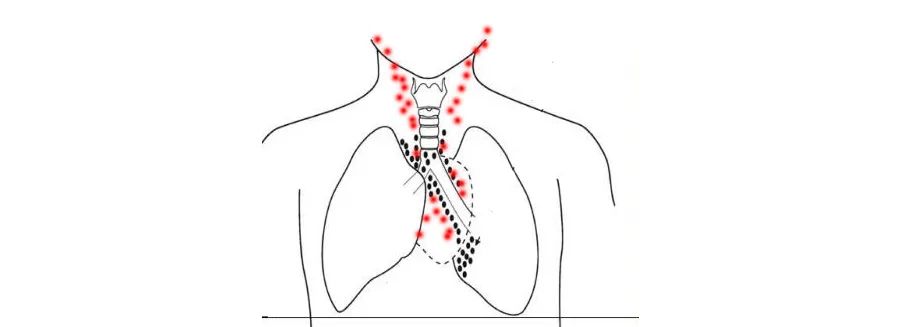

虽然肺泡破裂是诱发纵隔气肿重要原因(黑点),包括咽鼓管在内的颈部病变漏气(红点)也会引起颈气肿和纵隔气肿。

由于空气不能越过咽基底筋膜,气肿可能扩展到咽后间隙,刺激咽神经丛,导致咽喉痛。